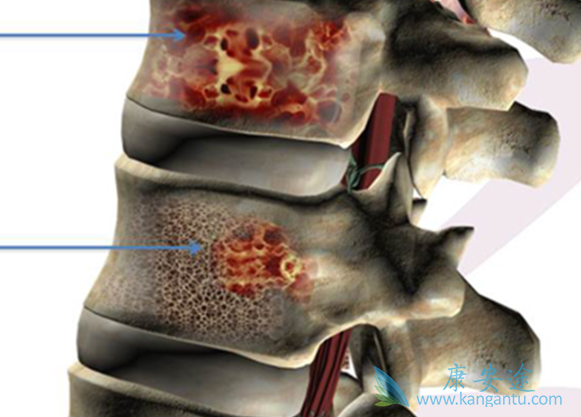

骨髓移植骨髓瘤能治好吗?多发性骨髓瘤发病率位居成人造血系统恶性肿瘤的第2位,迄今为止仍然不可治愈,那么问题来了,为什么不能通过类似于治愈白血病的移植方案来治愈骨髓瘤呢?首先谈谈移植,骨髓移植主要分成2大类:异基因移植(包括亲缘、非亲缘、脐带血和半相合移植)和自体移植,两者大相径庭,要达到治愈目的的是异基因移植。另一类是自体造血干细胞移植,基于的原理是:理论上放/疗剂量越大则抗肿瘤效果越好,但是对正常造血细胞的杀伤作用也很大,导致患者造血不能恢复。

为什么大部分骨髓瘤不采用异基因移植来治疗?临床不是不做、而是做得很少,最主要的原因是权衡利弊,发现对骨髓瘤患者采用这种治疗方案生存率并没有改善。根据美国SEER统计数据,骨髓瘤诊断时中位年龄是69岁,中国人从小样本统计看发病年龄要稍轻些,但是反过来中国人体质也差些。老年患者的异基因移植实在风险太大。所以,无论是NCCN指南还是中国骨髓瘤共识,尽管都不排斥异基因移植治疗骨髓瘤,但是指出:虽然这是一种治愈疾病的方式,但是风险实在太大,一定要仔细斟酌,仅仅适用于那些特别年轻的、预后特别差的、其它所有办法都无效的患者。

急性白血病是典型的肿瘤干细胞疾病,种子(白血病干细胞)不好而且疯狂生长,但是土壤(骨髓整体环境)还不错。于是干脆快刀斩乱麻,采用异基因骨髓移植这样强硬的的方式,换个健康的种子来治愈疾病。但是,骨髓瘤不一样,骨髓瘤干细胞和骨髓微环境都有问题,疾病又比较黏迁。因此,即使移植了健康的干细胞生长也会有问题,同时疾病没有像急性白血病那么凶险,可以采用一些相对缓和的方案和肿瘤展开长期拉锯战。骨髓瘤的治疗目标是:延长患者生存+提升生活质量,而不能一剂猛药直接把病人打趴下。